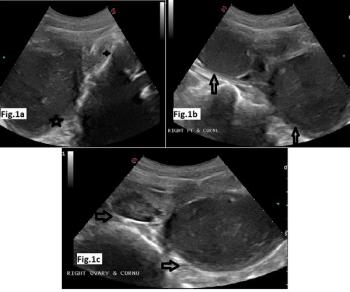

A young girl presented with complaints of dysmenorrhea and cyclic pelvic pain for one year. She had normal menarche and regular menstrual cycle.